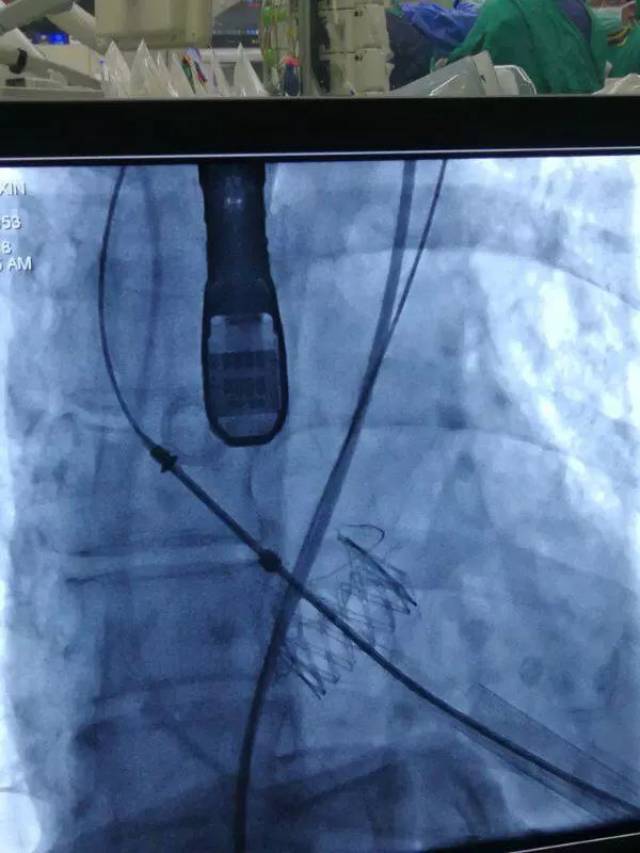

人工瓣膜释放

心脏瓣膜置换术

心脏瓣膜手术图片

人工心脏瓣膜

人工心脏支架图片